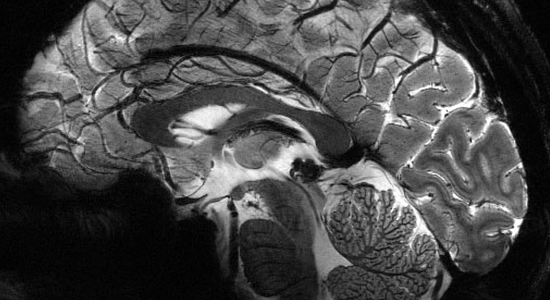

L'hémodynamique cérébrale

Son extraordinaire réactivité au CO2 et le mystère de l'autorégulation cérébrale